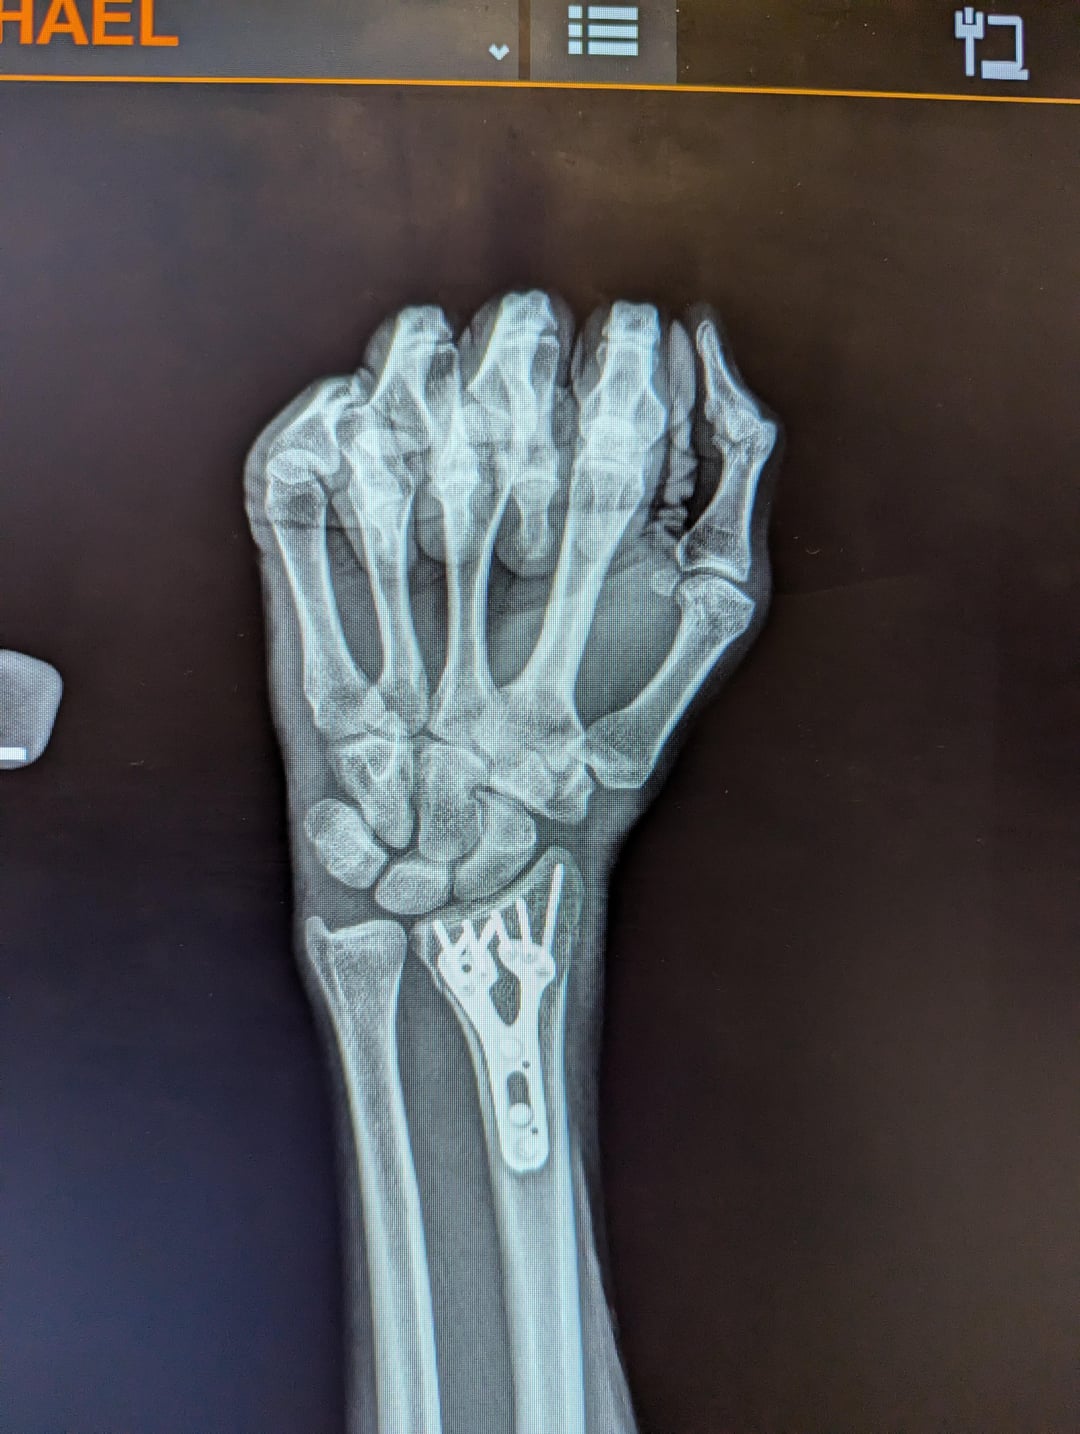

これまでに手首に約 5,000 ドルを費やしましたが、たくさんのお金を節約できてうれしいです。 "健康"。

(私の保険契約は自己負担額が最大 8,000 ドルです。保険が適用される前に、アメリカの民間保険を愛さなければなりません!!)